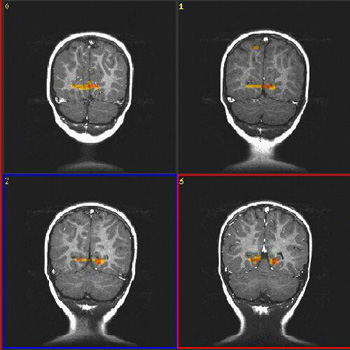

Niño normal de 18 meses de edad

Paradigma

n.° 2: |

ACTIVADO: Presentación de luces intermitentes a 8 Hz

DESACTIVADO: Nada. Paciente sedado con hidrato de cloral |

| Prueba T |

0,0005 |

3,3 |

| Imagen |

ACTIVADO-DESACTIVADO

DESACTIVADO-ACTIVADO

| Activación |

Hay activación bilateral de la corteza motora y "desactivación" de la región anterolateral de la fisura calcarina (periférico V1) como se observa en el caso n.° 3. La ubicación de esta respuesta es previsible, debido a que el tipo de estímulo usado aquí causa mayor activación de la retina periférica que de la fóvea. La activación de las áreas motoras a través de estímulos visuales es similar a la obtenida con la voz de la madre en el caso n.° 1. |